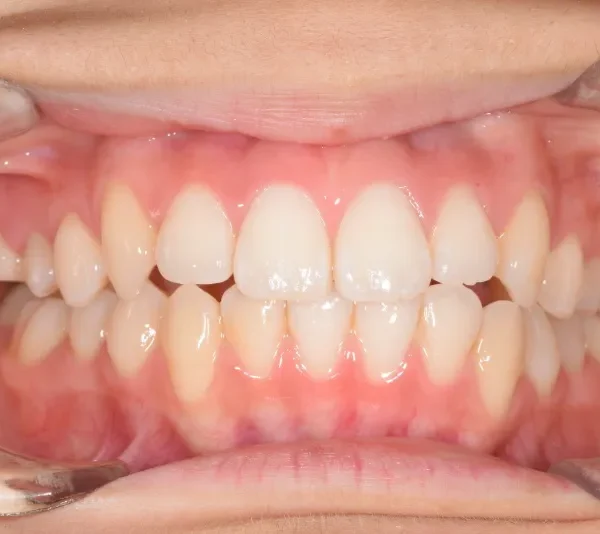

治療終了後